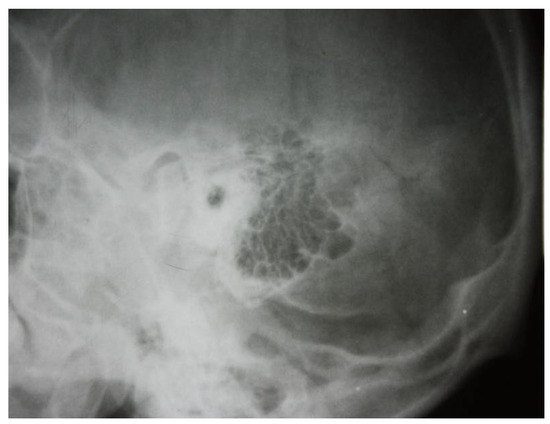

3.1.1. Conventional Radiology

3.1.2. Computed Tomography and Magnetic Resonance Imaging